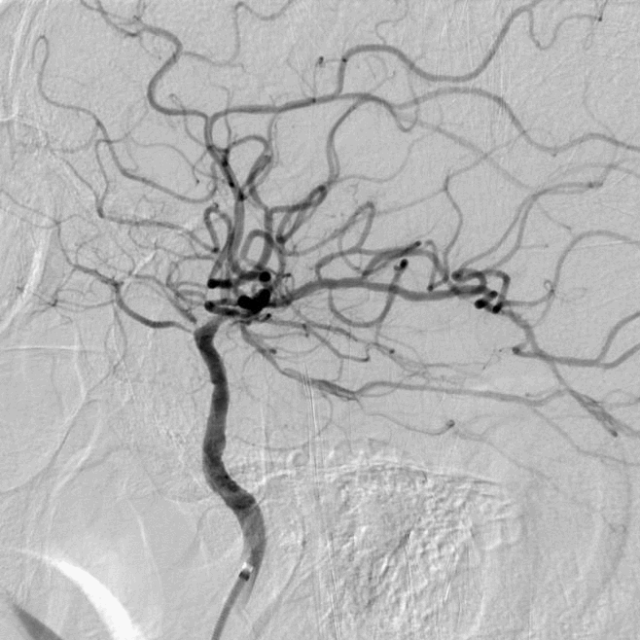

术前DSA

脑动脉CTA提示:左侧颈内动脉、大脑中动脉显影均较对侧显影明显变淡;后循环纤细。CTP提示:左侧额顶颞叶大片状低灌注区域,mismatch体积134ml,mismatch比值7.0。结合症状及影像学评估,左侧颈内动脉为导致缺血症状的病变血管。